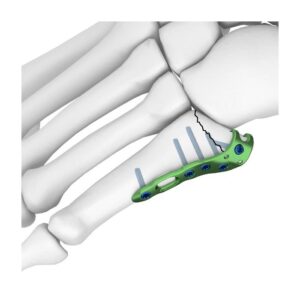

SISTEMA DE ARTROPLASTIA ANATOMICA DE LIGAMENTOS DEL PULGAR (ATLAS)

La técnica ATLAS está destinada a corregir la inestabilidad CMC del pulgar y facilitar un rápido retorno a la función mediante la colocación de fijaciones estables de anclaje basado en suturas en los sitios anatómicos de inserción del ligamento basal del pulgar.